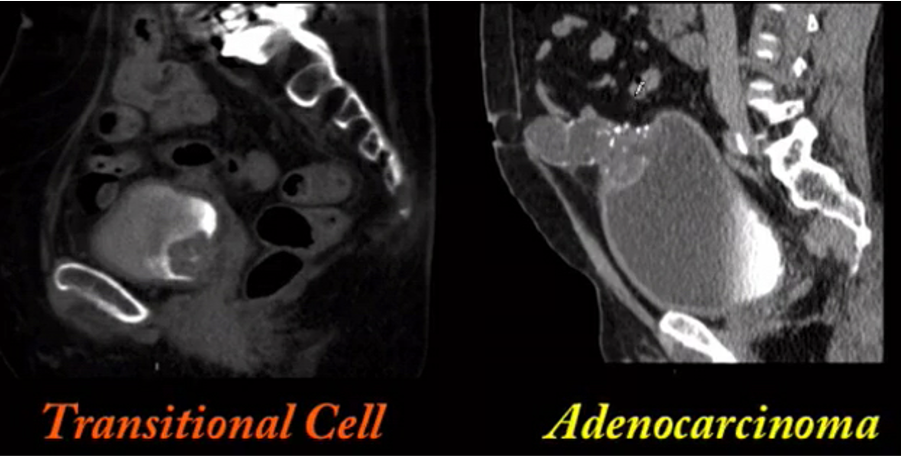

history of schistosomiasis

schistosomiasis